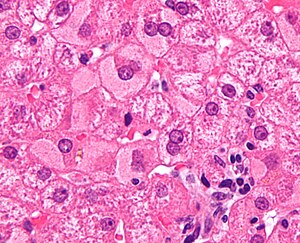

Coccidiomycosis

A.

B.

C.

D.

Coccidiomycosis. A. Note the granulomas in otherwise undisturbed liver (UL). B. Granuloma with centrally crowded cells & lady slipper macrophage nuclei. C. Center of granuloma with pyknotic macrophage nuclei, "necrotizing". D. Organisms on GMS stain.